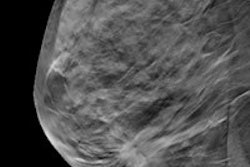

Whole-breast ultrasound (WBUS) is still a valuable adjunct to conventional mammography, even if digital breast tomosynthesis (DBT) is available, according to Yale University researchers, who discovered that WBUS found some cancers that DBT missed.

When added to conventional mammography, both WBUS and DBT can increase the cancer detection rate of breast screening. But there are still some invasive cancers that tomosynthesis misses -- and ultrasound can find these, said Dr. Regina Hooley, who presented the research at the RSNA 2013 meeting.

"Screening breast ultrasound is being more widely performed, primarily due to breast density notification laws," she told session attendees. "Because dense breast tissue can mask an underlying tumor, the false-negative rate of mammography in patients with dense breast tissue is higher compared to women without dense breast tissue."